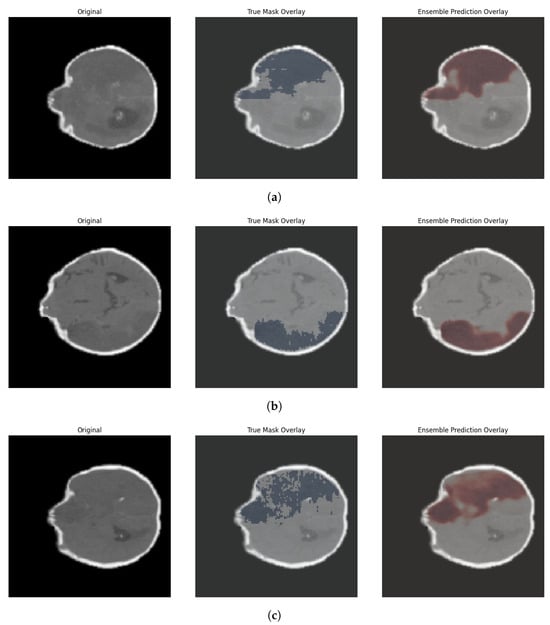

Figure 9 provides a visual representation of ischemic stroke segmentation results for three different patients.

Each row corresponds to a single CT slice and consists of three columns: first column—the original CT image, second column—overlay of the ground truth mask annotated by experts (in blue), third column—overlay of the ensemble model’s prediction (in shades of red). These examples demonstrate the model’s robustness across various lesion localizations and shapes. In the first case, the model captures an extended lesion area closely matching the ground-truth annotation in size. In the second example, there is a high degree of agreement between the prediction and the reference: the ensemble model accurately traces the contour of the affected region in the lower-right part of the brain. The third case also shows strong overlap between the predicted and ground-truth masks, particularly in the central and frontal regions. These visualizations confirm that the ensemble model is capable of accurately identifying ischemic lesions in different patients, maintaining a high degree of correspondence with expert annotations in both shape and location of the pathological regions. This result highlights the model’s clinical potential and its applicability in automated CT image analysis.

Figure 9. Examples of ischemic stroke segmentation with overlays of the ground-truth mask (blue area) and the predicted mask (red area) on CT slices from three patients (ac). Left to right: original image, ground-truth overlay, and ensemble model prediction overlay.